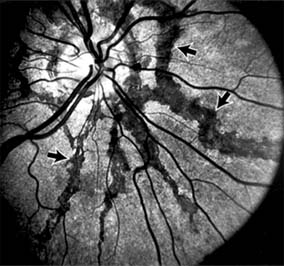

Presumed Ocular Histoplasmosis Syndrome (Figures 10-5, 10-6 and 10-7)

In this disease, serous and hemorrhagic detachments of the macula are associated with multiple peripheral atrophic chorioretinal scars and peripapillary chorioretinal scarring (see Chapter 7). The syndrome usually occurs in healthy patients between the third and sixth decades of life, and the scars are probably caused by an antecedent subclinical systemic infection with Histoplasma capsulatum. The macular detachments are due to subretinal neovascularization, and the visual prognosis depends on the proximity of the neovascular membrane to the center of the fovea. If the membrane extends inside the foveal avascular zone, only 15% of eyes will retain 20/40 vision. A macular scar may change over time, and 10% of patients with normal maculae will develop new atrophic scars in this region. The relative risk of developing macular subretinal neovascularization in the second eye of an affected patient is significant, and these patients should be instructed in the frequent use of the Amsler grid and the importance of prompt examination when changes are detected.

Figure 10-5

Figure 10-5: Presumed ocular histoplasmosis syndrome with active disease (large arrows) and an inactive pigmented macular scar (small arrow). Peripapillary pigmentation (curved arrow) is also present.

Figure 10-6

Figure 10-6: The early fluorescein angiogram shows an inactive hypofluorescent scar (small arrow) and the characteristic lacy hyperfluorescence of subretinal neovascularization (open arrows).

Figure 10-7

Figure 10-7: Late fluorescein leakage from macular subretinal neovascularization in a patient with presumed ocular histoplasmosis syndrome.

Argon laser photocoagulation of a subretinal neovascular membrane outside the foveal avascular zone in symptomatic patients is of value in preventing severe vision loss. The surgical removal of submacular membranes may prove useful in preserving vision.